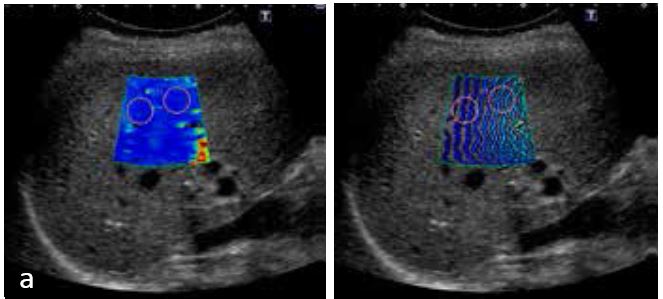

У пацієнтів з метастазами в печінці часто відображаються вищі значення швидкості зсувної хвилі. Швидкість зсувної хвилі у 50-річної жінки з метастазами в печінці (рис. 8) розраховували за допомогою Aplio 500 та Aplio i800. На Aplio i800, на зображенні у B-режимі чітко зображено паттерн «бичаче око» на ураженні. Карта швидкості чітко продемонструвала жорсткість внутрішньої частини ураження, а карта поширення показала, що розповсюдження були більш паралельними, що дозволило краще інтерпретувати отримання SWE. Тонкий промінь дозволяє отримати менше артефактів від таких структур, як судини.

Рисунок 8. Порівняння Aplio 500 і Aplio i800 у випадку 50-річної жінки з метастазами в печінці